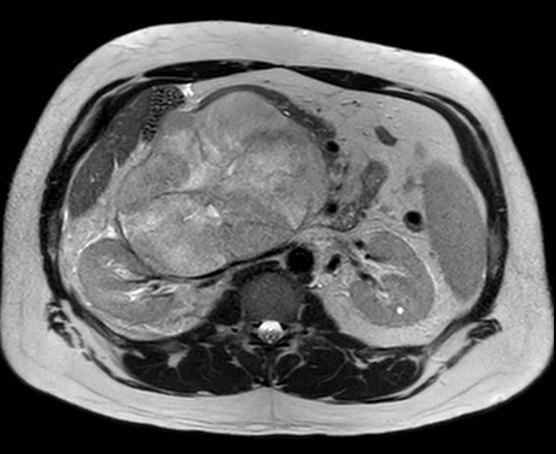

Sarcoma mỡ sau phúc mạc (Retroperitoneal liposarcoma)

16/03/2026